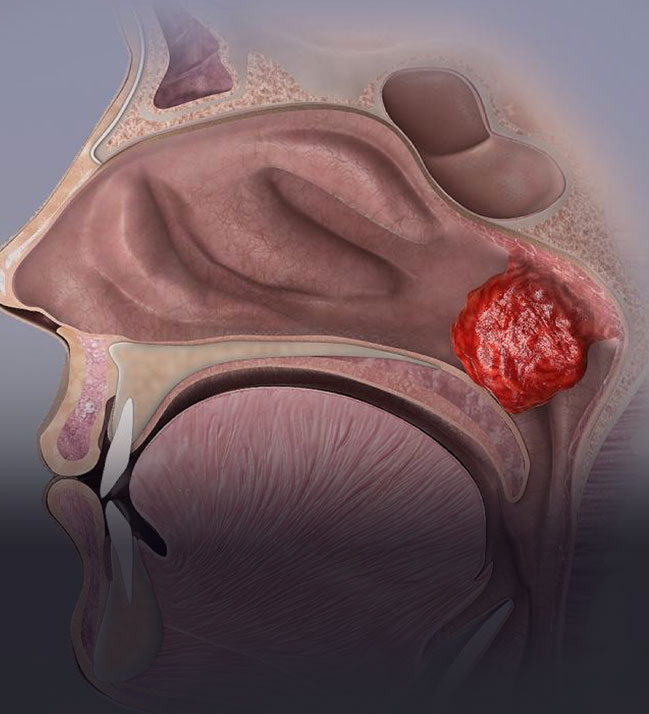

Nazal Polip Ameliyatı

Endoskopik Sinüs Cerrahisi